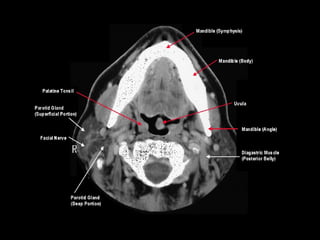

Radiographers use medical imaging equipment like X-rays and MRIs to produce images of patients' internal structures and organs. They are responsible for positioning patients, operating scanning machines, and ensuring quality images. Radiographers must have strong attention to detail, excellent communication skills, and the ability to work well under pressure to accurately capture anatomical features and diagnose any abnormalities.